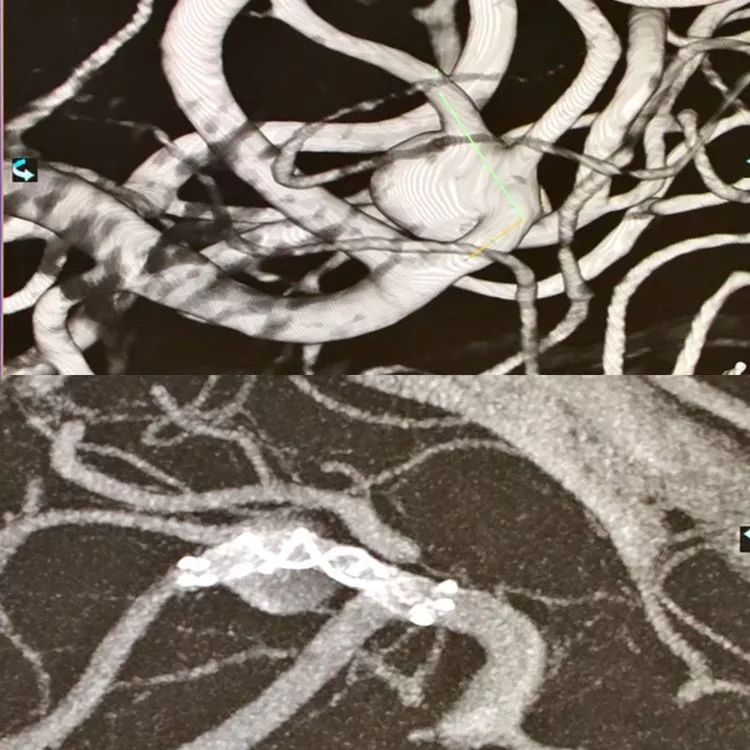

CASE 5 AN

-WEB是治疗分叉部动脉瘤的新武器

-WEB治疗复发的原因分析:一种解释是压缩造成的,wakhloo认为另外一个可能的原因是血栓的机化,机化的血栓可能牵拉WEB造成复发